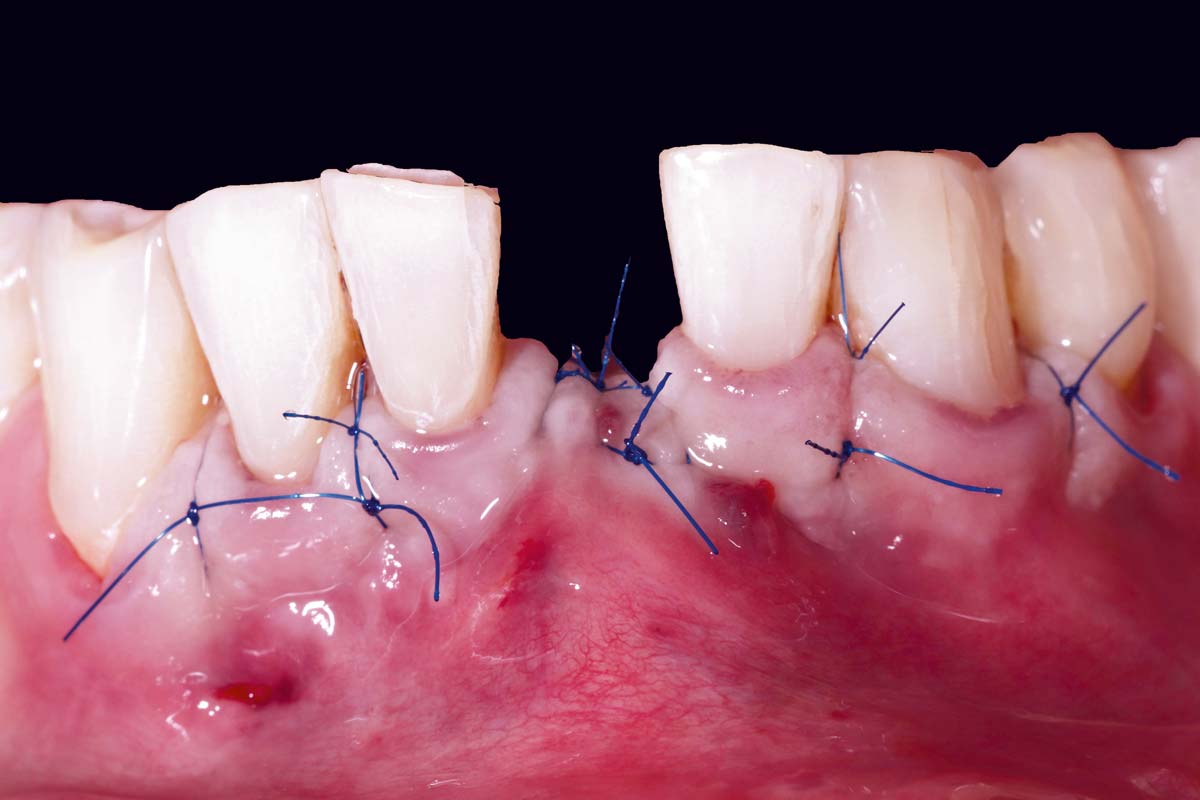

Immediately placed implant covered with permamem®. permamem® passively immobilized by sutures and intentionally left exposed to the oral cavity.